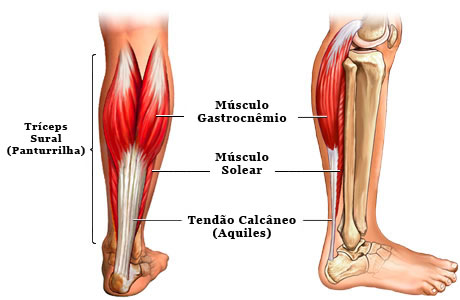

O tendão calcâneo, popularmente chamado de tendão de Aquiles, é o tendão mais espesso e resistente do corpo humano. Ele é formado pela porção tendinosa dos três ventres musculares que formam a panturrilha, o gastrocnêmio medial, ogastrocnêmio lateral e o solear. Na sua porção mais baixa insere-se no calcâneo (osso do calcanhar).

O tendão calcâneo é o mais importante tendão flexor do tornozelo. Sua ação é primordial para o desprendimento do pé na marcha, para dar arrancada e força na corrida e no salto. Além disso, ele absorve grande parte do impacto na fase de aterrissagem após o ato de saltar.